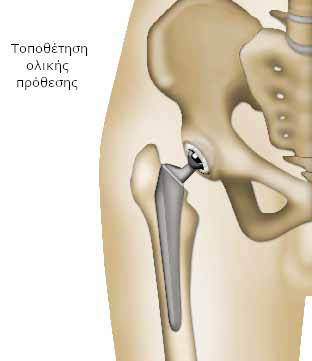

Αντιθέτως, όταν διαπιστώσει ολική καταστροφή των επιφανειών, αφαιρεί τις περιοχές που έχουν υποστεί βλάβη και προχωρεί στην αντικατάστασή τους με τεχνητά μέρη (πρόθεση), που εξασφαλίζουν την ανώδυνη λειτουργία της άρθρωσης. Αυτή η επέμβαση, που παρουσιάζεται σε αυτό το φυλλάδιο, ονομάζεται αρθροπλαστική ισχίου.

Ο χειρουργός προτείνει την αντικατάσταση των φθαρμένων περιοχών της άρθρωσής σας με τεχνητά μέρη (πρόθεση). Στην ιατρική γλώσσα, ονομάζεται αρθροπλαστική ισχίου.

Όταν πρέπει να αντικατασταθούν όλα τα μέρη της άρθρωσης (ολική πρόθεση), ο χειρουργός προσθέτει ένα τμήμα σε σχήμα κούπας (το κυπέλλιο), που στερεώνεται στην κοτύλη.

Λειτουργία

Το πρόβλημα της αρθρίτιδας αντιμετωπίστηκε. Η κεφαλή της πρόθεσης θηλυκώνει στην κοτύλη (στην περίπτωση της πρόθεσης μηριαίας κεφαλής) ή στο κυπέλλιο (στην ολική πρόθεση), και λειτουργεί όπως η φυσιολογική άρθρωση.